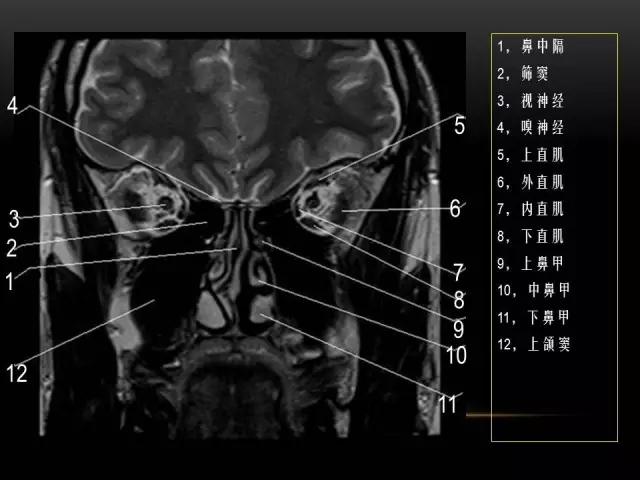

下文是在MRI下眼部及鼻窦的冠状位解剖图谱。